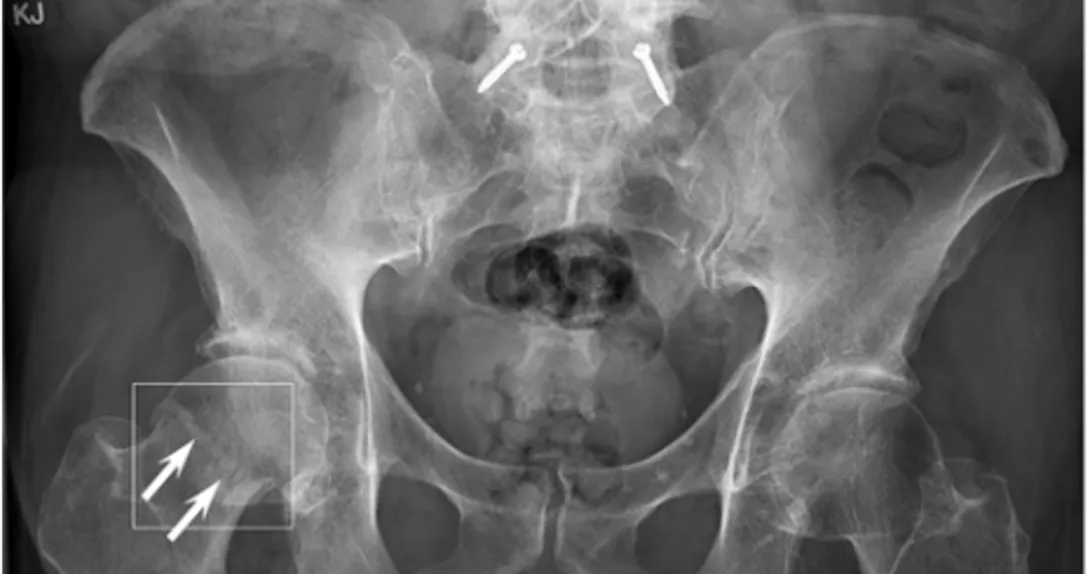

BoneView uses artificial intelligence to detect potential fractures and sends results to radiologists for confirmation. The software received a CE mark in Europe in March 2020.

GLEAMER is pitching the FDA clearance as a way to limit diagnostic error without overloading radiologists.

"Radiologists' workload has doubled in the past two decades, and despite technological progress, they must analyze hundreds more images every day, requiring the readings to be highly reliable," Dr. Ali Guermazi, PhD, chief of radiology at the VA Boston Healthcare System and leader of the company's clinical trial for its FDA submission.

"The assistance of AI should allow us to improve the specificity of the complementary exams prescribed after the radiography, to avoid delays in care, and to direct patients into the right therapeutic pathway. Our study was focused on fracture diagnosis, and a similar concept can be applied to other diseases and disorders."